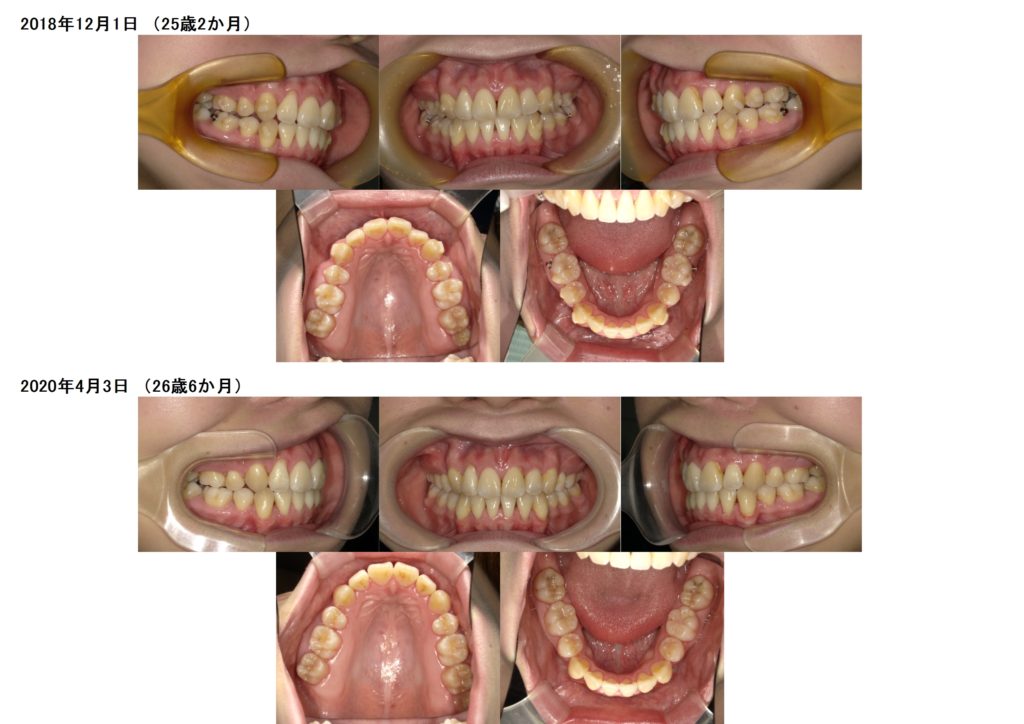

↑この患者様は上下の歯を2本ずつ抜歯しています。

上の顎にアンカースクリューを使用し、抜歯した際に6番目の歯が寄ってこないためにしています。

このように土台を整えつつ、ブラケットを使用し調整をしていきます。

奥歯の噛み合わせを確立したら、あとは前歯部の噛み合わせを合わせ引っ込めていきますよ

隙間が埋まったら治療が終わりです☆

↑治療前、治療後の口腔内写真の比較です。

上下の顎のアーチを整えながら、抜歯した隙間を利用し噛み合わせの深さや突出している部分も改善しているのが分かると思います。

約2年間のブラケット治療になりますが、お口の中もとても変化します。突出している方だと横顔のラインも変わりますので、